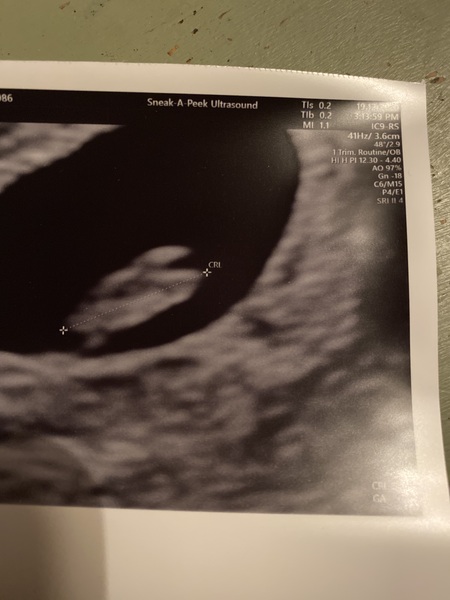

Scan today backfired before Christmas and telling relatives ( who I still get to see) . Scan has put me back to 6wk 1/2 days. But that is feasible as I have no idea when I had last period as they aren’t regular at all and hadn’t been overly trying to get pregnant. Got negative test on 22nd nov & positive on 26th November, so I think that still fits in . So either I’m just later than I thought or bean has stopped growing. Have to go for another scan in 7-10 days but I’m ok about that... just cross I can’t give family a definite yay I’m pregnant. I’ll keep you guys updated.

Same here but no heartbeat .... early scan yesterday backfired before Christmas and telling relatives ( who I still get to see) . Scan has put me back to 6wk 1/2 days and no heartbeat. I had guessed roughly 7-8. But that is feasible as I have no idea when I had last period as they aren’t regular at all and hadn’t been overly trying to get pregnant. Got negative clear blue digital test on 22nd nov & positive on 26th November, (1-2 weeks) and then a week later @ 2-3 so I think that still fits in? Only just?

So either I’m just later than I thought or bean has stopped growing. Have to go for another scan in 7-10 days aswell . I’m ok about that... just cross I can’t give family a definite yay I’m pregnant. More like yay I’m pregnant but don’t get your hopes up...grrr. Also being slightly demented!!!

Hi @Kinsters slow really was slow - she couldn't measure using the ultrasound but estimated it at around 67 bpm. I have barely read any positive stories of heart rates that slow. I could see 'pulsations' as the sonographer described them but it wasn't that strong flashing that I've seen in scans with my dc. But the size was just right. Sorry to hear you also had a previous loss. It's so tough in the first 12 weeks. I also had a mc but the baby had never developed. I feel this is a harder wait and sadder now I've seen the heartbeat.